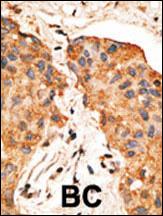

Formalin-fixed and paraffin-embedded human cancer tissue reacted with the primary antibody, which was peroxidase-conjugated to the secondary antibody, followed by DAB staining. This data demonstrates the use of this antibody for immunohistochemistry; clinical relevance has not been evaluated. BC = breast carcinoma; HC = hepatocarcinoma. |